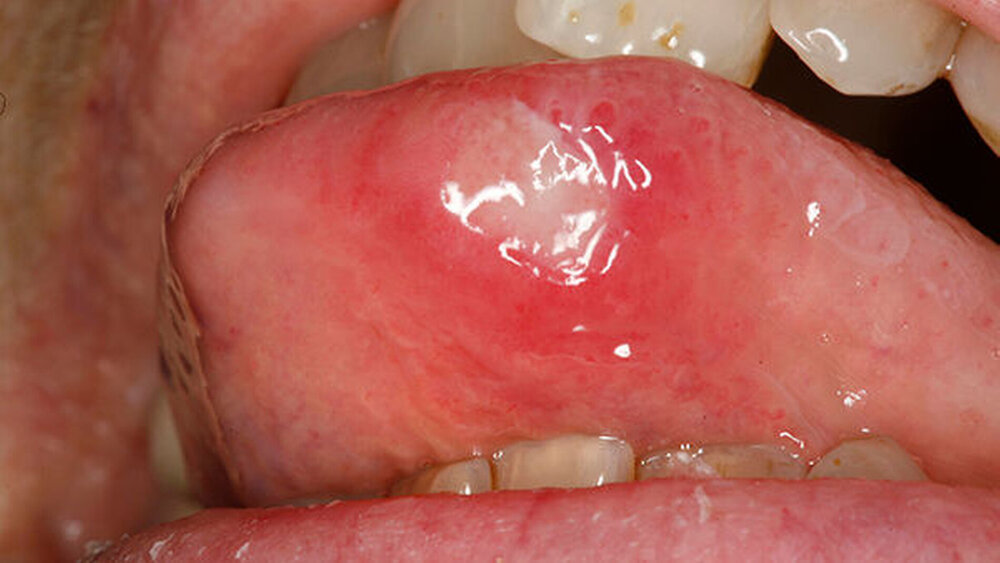

Die Phasen der oralen und pharyngealen Aphthose sind gekennzeichnet durch ein bis zu 24-stündigesProdromalstadiummit Kribbeln, Spannungsgefühl, Brennen, Rauigkeit, an das sich

eine bis zu drei Tage dauerndepräulzeröse Phasemit einem inflammatorischen Erythem beziehungsweise dem Auftreten einer indurierten Papel anschließt.

Das darauffolgende ein bis 16 Tage dauerndeulzerative Stadiumist durch die typische fibrinbelegte Ulzeration mit aufgeworfenem Rand gekennzeichnet.

Die sich daran anschließendeAbheilungsphasekann vier bis 30 Tage andauern.